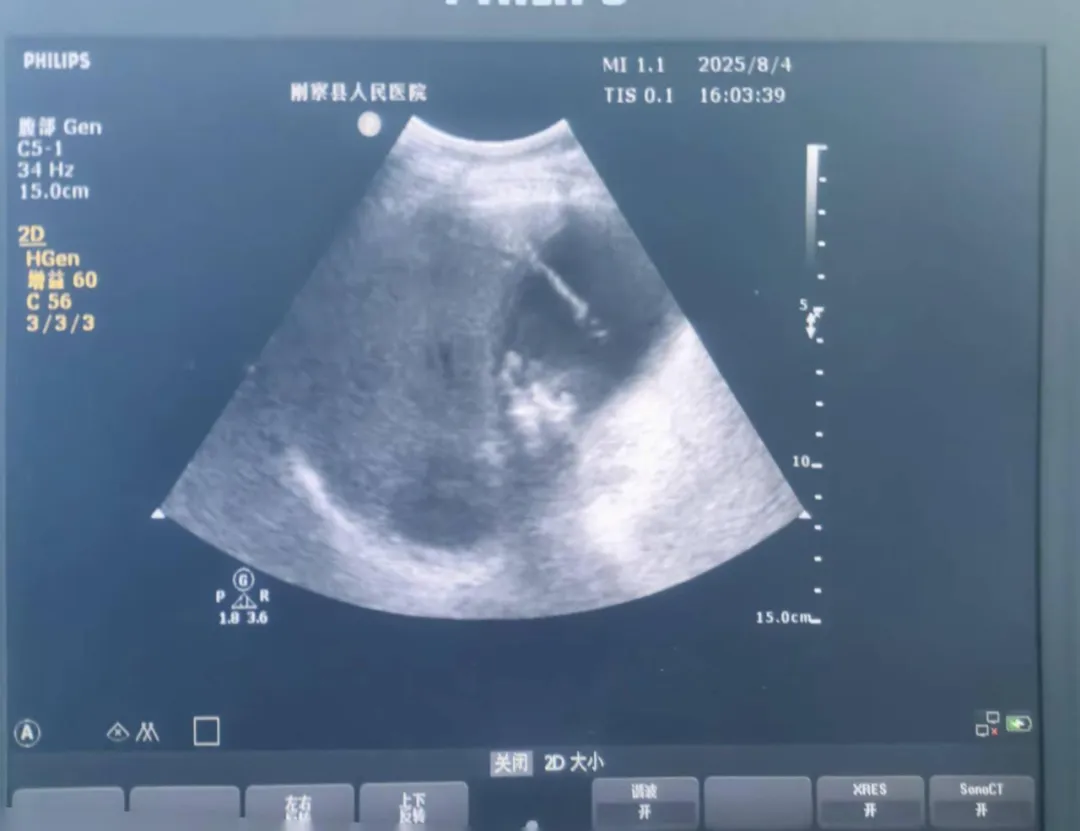

近日,在海拔3300米的青海省刚察县,刚察县医共体总院副院长(援青)侯旭克服严重高原反应,带领当地外科团队,成功完成该县首例超声引导下经皮经肝胆囊穿刺引流术(PTGD)。这标志着刚察县在肝胆外科急危重症诊疗领域取得重大突破。

日前,一名七旬高龄患者因胆囊结石伴急性化脓性胆囊炎入住刚察县医共体总院。保守治疗后,患者腹痛持续加重,病情危急,随时可能发展成感染性休克。面对患者转诊风险大、时间紧迫的难题,侯旭迅即组织外科团队进行评估讨论。鉴于患者高龄及危重状况,团队果断决定实施创伤小、见效快的PTGD术。该方案尤为适合基础条件受限的高原地区急症处理。

手术中,侯旭坚持“援青即传帮带”理念,边操作边教学。从超声定位、穿刺点选择到置管固定,每个关键步骤他都细致讲解要点。在他的精准指导下,本地外科医生们逐步掌握了核心技术。整个手术仅耗时20分钟,成功引流出大量脓性胆汁,患者腹痛随即缓解,生命体征平稳。